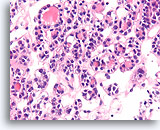

Afbeelding 83

Medullair schildkliercarcinoom, schildklier FNA, celblok.

Een solide groeipatroon is aanwezig met een fragment amyloïde. Let op de excentrische kernen met een plasmacytoïde uiterlijk en lichte nucleaire variabiliteit.

40X

Afbeelding 83

Medullair schildkliercarcinoom, schildklier FNA, celblok.

Een solide groeipatroon is aanwezig met een fragment amyloïde. Let op de excentrische kernen met een plasmacytoïde uiterlijk en lichte nucleaire variabiliteit.

40X